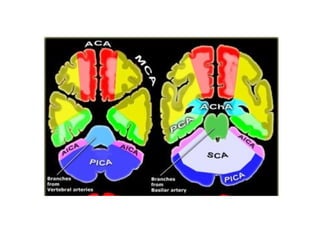

Vascular territories of the brain

Left ACA territory

Right ACA territory

Right MCA territory

Left PCA territory

SCA territory

Right AChA territory

Right lateral lenticulostriate artery territory